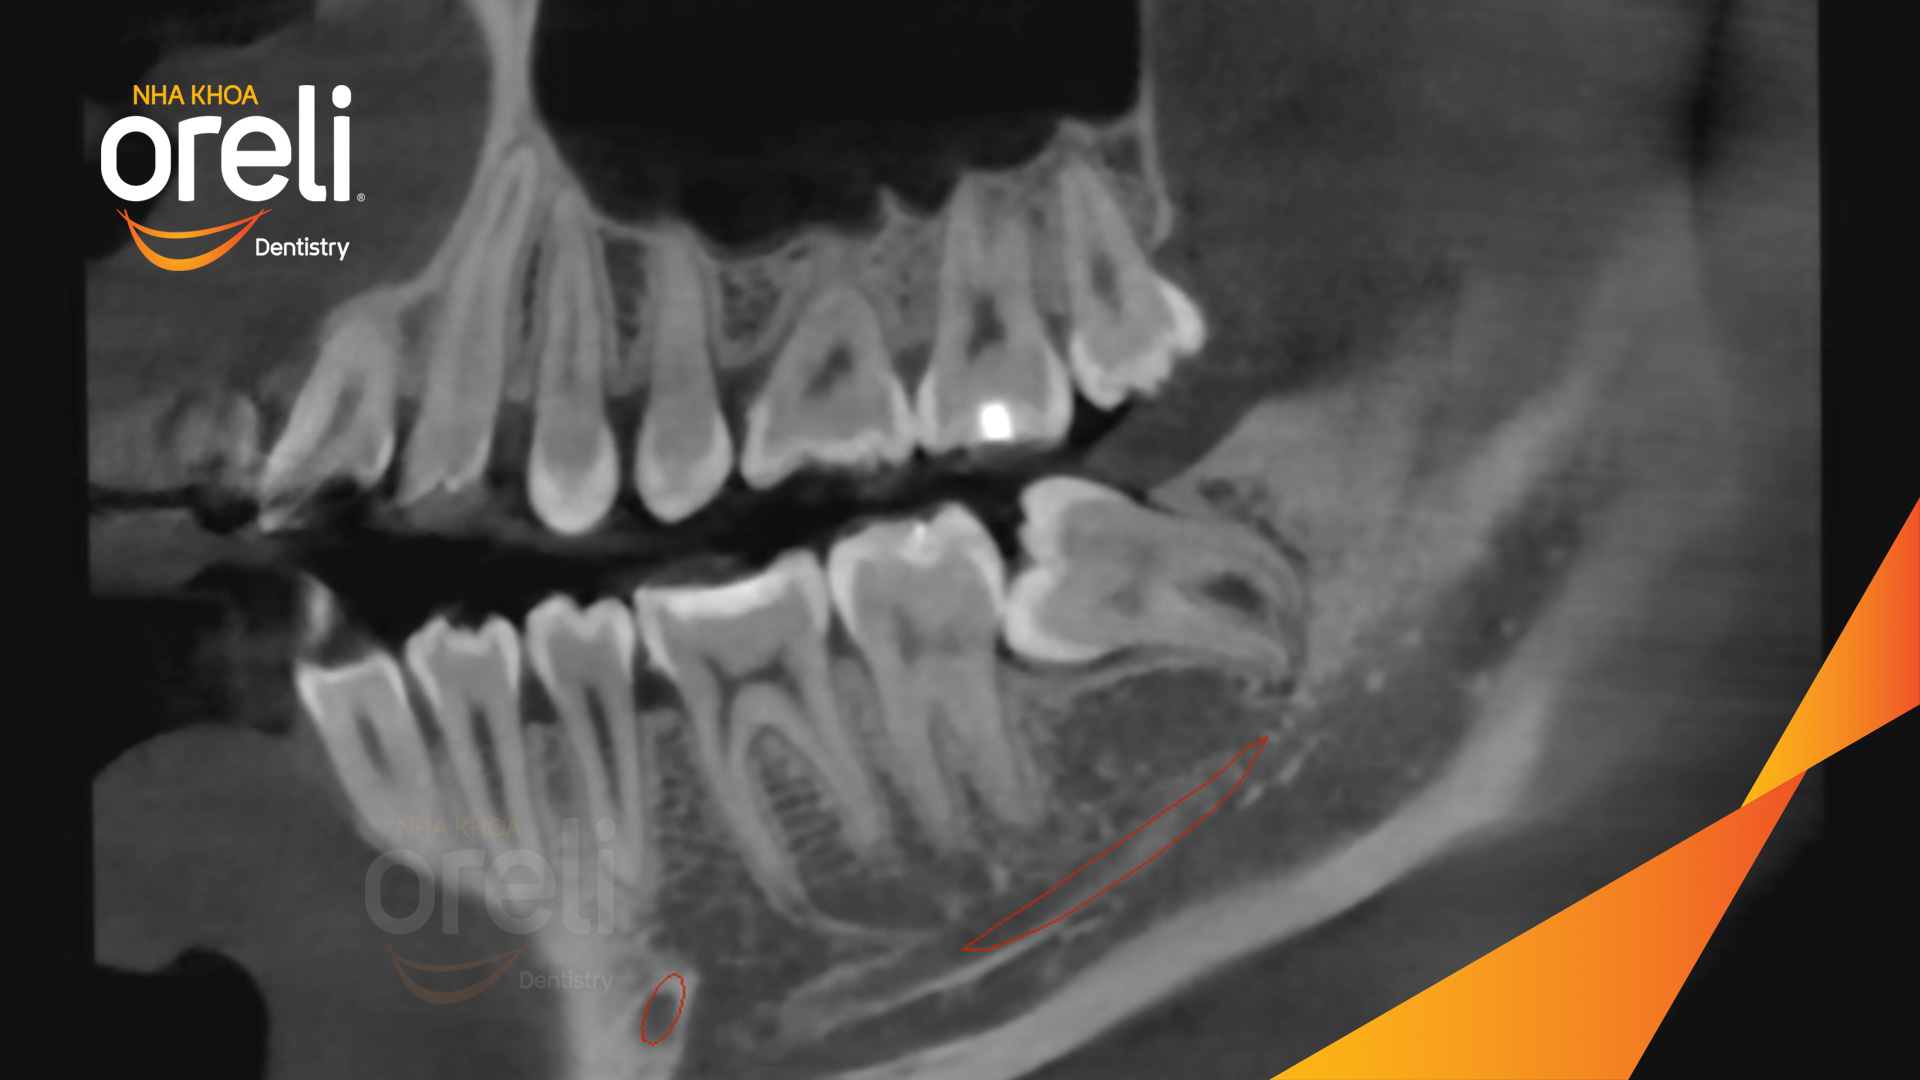

Ca nhổ răng khôn ảnh hưởng răng bên cạnh – Điều trị tại Oreli

Nhổ răng khôn

Mọc lệch

Xem thêm